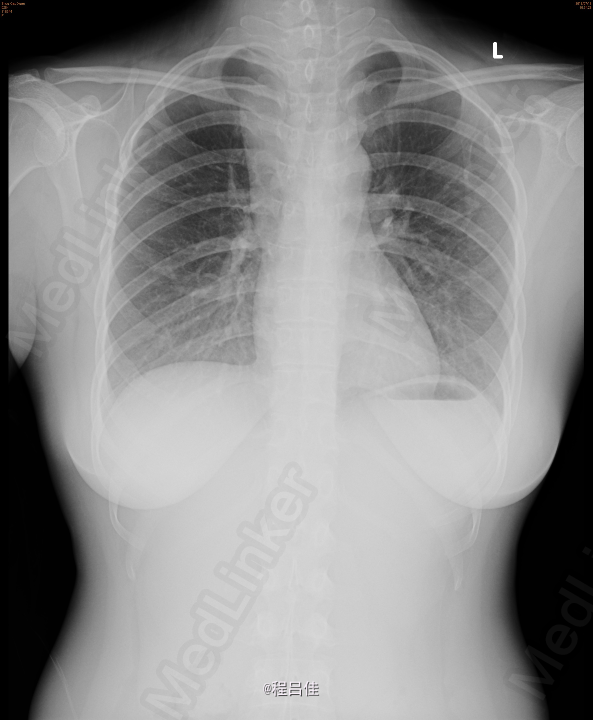

查体: 1.T37℃, P90次/分,R20次/分,BP120/80mmHg。颈软,外形对称,未见颈静脉怒张,未见血管搏动,气管偏左。右侧甲状腺II度肿大,内扪及数个结节,质硬,边界不清,无压痛,随吞咽上下移动。左侧(-)。颈部淋巴结未扪及。突眼征(-),双手震颤试验(-)。 辅查: 甲工5项正常、肺肿瘤组合(-)、血清降钙素原PCT1.31 ng/mL ↑ 、术后钙Ca 1.83 mmol/L ↓ 2.甲状腺US: 右叶甲状腺CA,向胸骨后延伸并侵犯右侧颈静脉起始段;左叶甲状腺滤泡囊肿。 双侧颈部未见异常肿大淋巴结。 3.胸片: 右上纵隔增宽,气管受压向左侧移位 4.心脏彩超:二尖瓣前叶脱垂并关闭不全(轻微),右房近上腔静脉入口处团块状回声。 5.PET-CT:甲状腺右叶及峡部肿块(向下延伸至胸骨上缘水平,邻近气管受压),代谢活跃,考虑恶性肿瘤,右侧颈内及购买起始段、右头臂静脉、上腔静脉、右心房上部节段性代谢增高,考虑癌栓形成。甲状腺左叶小结节,代谢未见异常,考虑结节性甲状腺肿或小囊肿。 6.术中冰冻快速切片报告: (左侧甲状腺)送检3.5x2.5x2cm暗红组织一块,切面暗红,无明显结节。冰冻快速切片报告镜下:结节性甲状腺肿,未见肿瘤。